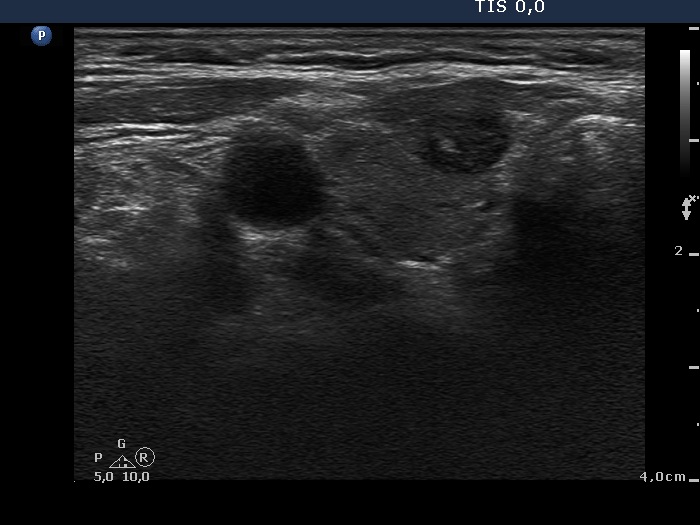

Ultrasonography. There was a hypoechogenic nodule presenting microcalcification in the ventromedial part of the right lobe. Corresponding to the palpable mass in the right submandibular area, a lymph node was found. The node did not present hilum.